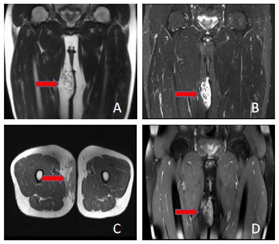

MRI影像表现:右大腿上段内侧皮下脂肪层内类椭圆形异常信号灶(图1),范围约74 mm×26 mm×87 mm,边界不清,呈浸润性生长,T1WI等稍高信号,T2WI稍高信号,T2WI/FS呈高亮信号,增强后明显强化,其内部可见夹杂脂肪信号灶。右侧腹股沟区见多发异常肿大淋巴结(图2),最大者大小约27 mm×19 mm,呈T1WI等稍高信号,T2WI/FS呈高亮信号,增强后均匀明显强化。MRI诊断:右大腿上段内侧皮下脂肪层内异常信号,良性病变多考虑,血管瘤?血管脂肪瘤?右侧腹股沟区多发肿大淋巴结,建议进一步穿刺活检。

头颈部木村病,影像学表现结合特征性的实验室检查,一般诊断不难,但当木村病发生在一些少见部分,例如四肢、腋窝、腹股沟区时,应该与相应部位的常见病变鉴别。本例报道中的发病部位比较罕见,发病形式比较有特点,表现为大腿上段内侧皮下病灶伴同侧腹股沟区多发淋巴结肿大,因两者信号特点基本一致,考虑一元论,大腿上段内侧皮下病灶表现为边界不清的肿块,T2压脂像信号高亮,无明显的囊变、坏死、出血成分,增强后明显强化,大腿病灶周围脂肪层内出现索条影或网格状浸润影,对应组织学上病灶内软组织水肿和炎症细胞的混合改变,既往几例上肢木村病的报道[3,4]也有类似影像学表现,病灶亦可包绕皮下走行的血管或神经,较大时可推压邻近肌肉,但是血管、神经及肌肉没有直接侵犯的征象,同侧腋窝也出现了淋巴结肿大,肿大淋巴结信号均匀,没有坏死。